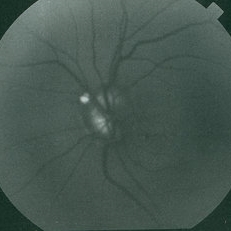

Drusen of Optic Nerve Head

Mar 26 2019 by Gary R. Cook, MD, FACS

Left eye of a 60-year-old white male with bilateral optic disc drusen; VA= 20/15.

Imaging device: Topcon VT-50

Condition/keywords: drusen of optic disc, optic disc drusen